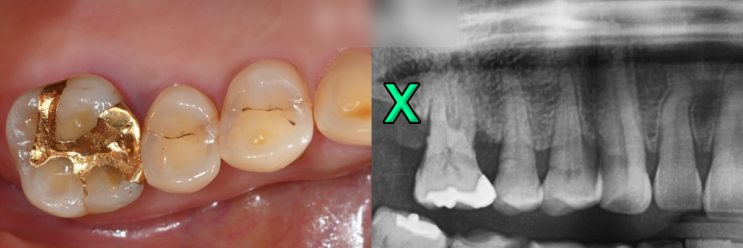

오래된 아말감 충치, 수은, 변색이 걱정된다면? 레진 인레이로 개선 +치경부마모증 치료방법은? 서대문치과에서 알려드립니다

안녕하세요, 대표원장 조민기입니다. 어렸을 때 90년대생까지는 충치치료를 받았던 분들이라면 아말감이라...